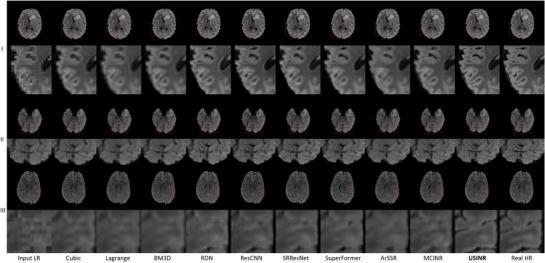

To achieve super-resolution for on-board MRI, this study proposed a universal anatomical mapping and patient-specific prior implicit neural representation (USINR) framework. Unlike traditional methods that interpolate solely based on individual on-board MR images, USINR can fully utilize the patient-specific anatomical information from a high-resolution prior MRI. In addition, USINR leverages knowledge about universal mapping between population-based prior MRIs and on-board MRIs, elevating the upper bound of super-resolution performance and enabling faster on-board fine-tuning.

USINR was evaluated on three datasets, including IXI, BraTS, and an in-house abdominal dataset. It achieved state-of-the-art performance on all of them. For example, on the BraTS dataset, USINR was trained on 1151 paired training samples (for universal anatomical mapping) and tested on 50 patients. It achieved average SSIM, PSNR, and LPIPS scores of 0.9656, 37.12, and 0.0214, respectively, significantly outperforming the published state-of-the-art method SuperFormer, whose corresponding scores were 0.9488, 35.83, and 0.0388. Furthermore, USINR can complete patient-specific training in less than one minute, rendering it a favorable solution in time-constrained ART workflows. In addition to large-scale dataset evaluations, a case study was conducted on an in-house patient at UT Southwestern Medical Center. This case study included two MRI scans (a prior scan for plan simulation and a new one for on-board imaging) from a single patient with a long interval between two scans, during which the tumor size underwent a significant change. Despite these substantial anatomical changes between prior and on-board imaging, USINR was able to accurately capture the change in tumor size, highlighting its robustness for clinical applications.

结果

USINR在三个数据集上进行了评估,包括IXI、BraTS和一个内部腹部数据集。在所有这些数据集上,它都取得了领先的性能。例如,在BraTS数据集上,USINR在1151对训练样本(用于通用解剖映射)上进行训练,并在50名患者上进行测试。它分别实现了平均结构相似性指数(SSIM)、峰值信噪比(PSNR)和学习感知图像补丁相似度(LPIPS)分数为0.9656、37.12和0.0214,显著优于已发表的领先方法SuperFormer,其相应分数分别为0.9488、35.83和0.0388。此外,USINR可以在不到一分钟的时间内完成患者特异性训练,使其成为时间受限的ART工作流程中的理想解决方案。除了大规模数据集评估外,还在德克萨斯大学西南医学中心的一名内部患者身上进行了案例研究。该案例研究包括来自一名患者的两次MRI扫描(一次用于计划模拟的先验扫描和一次用于机载成像的新扫描),两次扫描之间间隔较长,在此期间肿瘤大小发生了显著变化。尽管先验成像和机载成像之间存在这些显著的解剖结构变化,USINR仍能够准确捕捉肿瘤大小的变化,突出了其在临床应用中的稳健性。